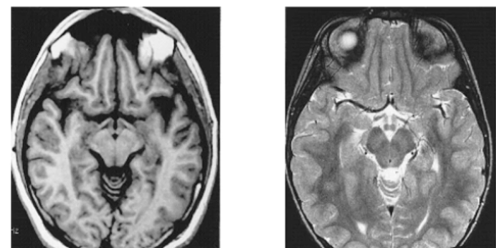

16

Q

which one is T1 and which is T2

A

L: T1

R: T2